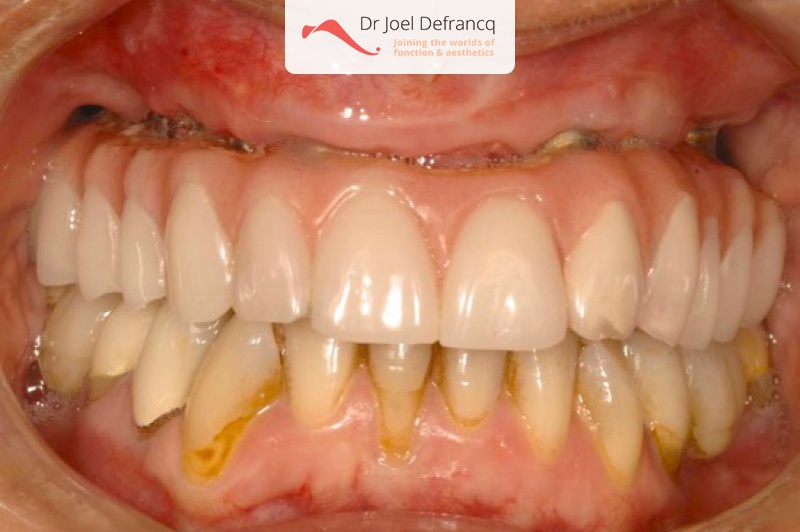

Esther: new teeth in a week - implants

Behandeling tandheelkundige implantaten

- Vaste tanden op implantaten (bovenkaak)

- Vaste tanden op implantaten (onderkaak)